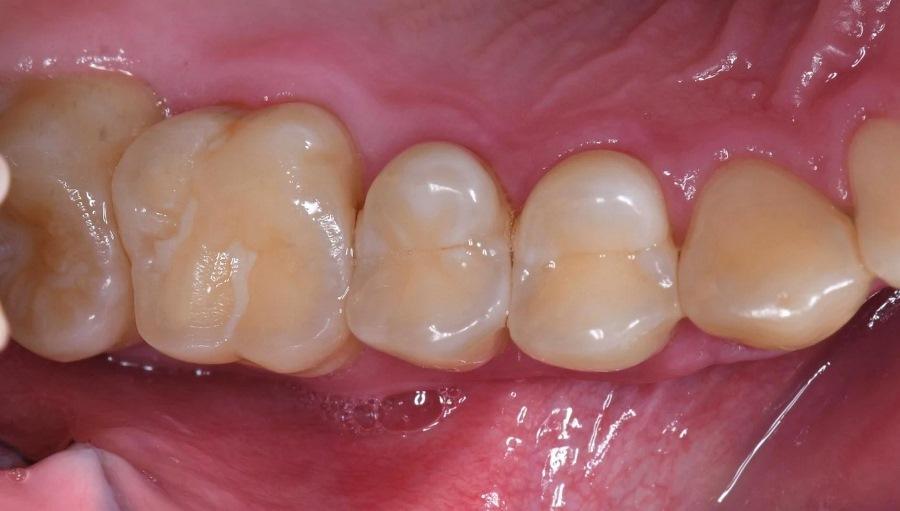

Фото 12 – Фото 15. Двенадцать месяцев после лечения. Через 12 месяцев после операции (Фото 12); обратите внимание на улучшение качества тканей.

Фото 12 – Фото 15. Двенадцать месяцев после лечения. Через 12 месяцев после операции (Фото 12); обратите внимание на улучшение качества тканей. Окклюзию также оценивали через 6 и 12 месяцев после лечения, и при необходимости выполняли коррекцию (Фото 13).

Фото 12 – Фото 15. Двенадцать месяцев после лечения. Через 12 месяцев после операции (Фото 12); обратите внимание на улучшение качества тканей. Окклюзию также оценивали через 6 и 12 месяцев после лечения, и при необходимости выполняли коррекцию (Фото 13). Периапикальный рентгеновский снимок (Фото 14) и КЛКТ-изображение (Фото 15) через 12 месяцев после лечения, показывающие регенерацию кости в области фуркации зуба № 2.6 с продолжающимся улучшением костной плотности. Клиническая глубина зондирования с вестибулярной поверхности зуба № 2.6 улучшилась с 12 мм до 3 мм. Ожидается, что регенерация кости будет продолжать улучшаться до 3 лет после лечения по протоколу LANAP, причем большая часть регенерации происходит в течение первого года.